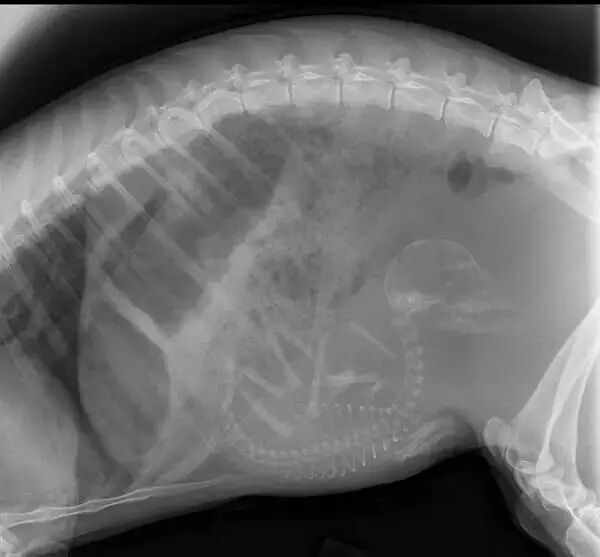

怀孕的猫

奇趣百科 涨姿势 · 17种怀孕动物X光照片,大开眼界!-怀孕期